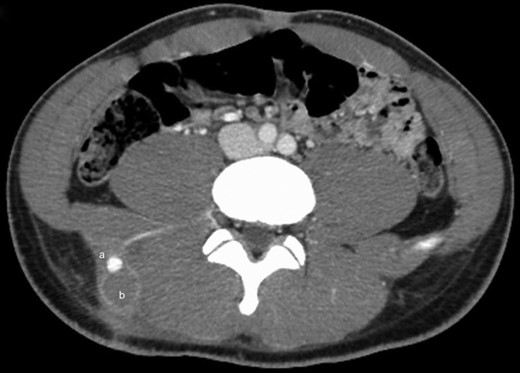

Examination on admission revealed an actively bleeding 2-cm wide stab wound in the right lumbar paraspinal region. A contrast-enhanced CT of the pelvis showed an enhancing lesion consistent with a pseudoaneurysm extending from a branch of a right lumbar artery (Figs 1 and 2). The patient was transferred to the interventional radiology suite where angiography confirmed the diagnosis (Fig. 3). The pseudoaneurysm was then successfully embolized using platinum microcoils (Fig. 4), which were positioned in the lumbar artery, proximal and distal to the origin of the pseudoaneurysm. The patient tolerated the procedure well and was discharged the following day without any further complication.

Axial cut from the same contrast-enhanced CT scan of the lower abdomen and pelvis showing a 1.6-cm bilobed, enhancing lesion, consistent with pseudoaneurysm, presumably extending from a branch of a right lumbar artery (a).